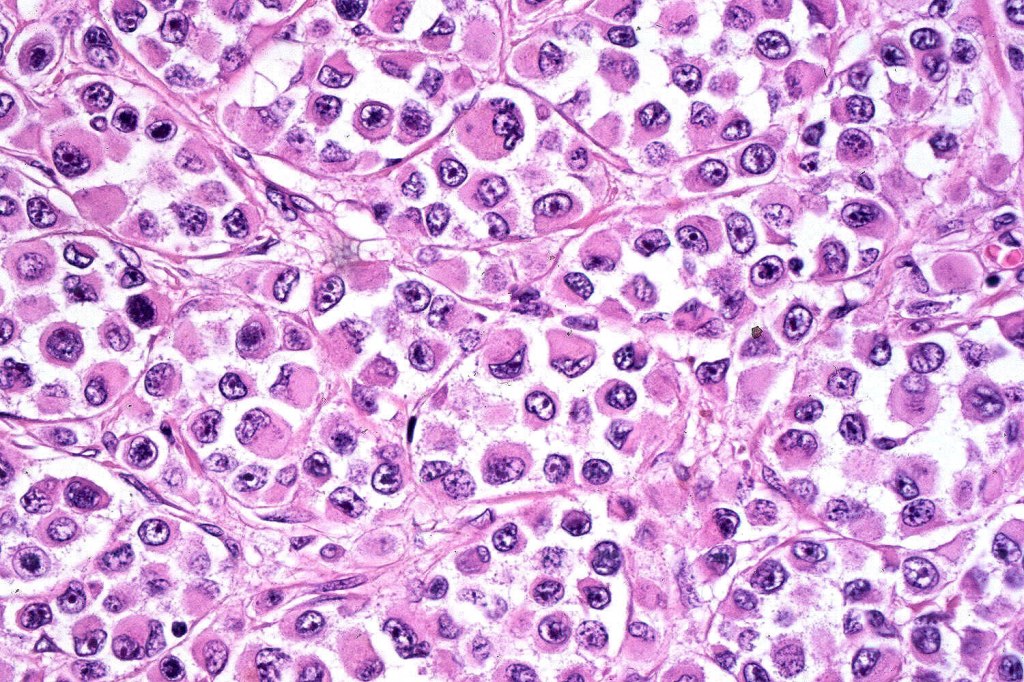

•Characterized by pleomorphic tumor cells with large eosinophilic, hyaline globular inclusions and eccentric vesicular nuclei containing prominent nucleoli, mitoses often conspicuous

•Inclusions predominantly composed of vimentin intermediate filaments

•Immunophenotype is variable with possible loss of expression of one or more of the usual melanocytic markers including S100 & SOX10 (occasionally), HMB45/MART-1 (not uncommon), MITF & tyrosinase

•A broad panel is recommended to detect positivity in one or more of these markers

•Loss of INI1 expression described

•Vimentin & sometimes desmin expression positive in the inclusions

•Occasional weak keratin expression reported